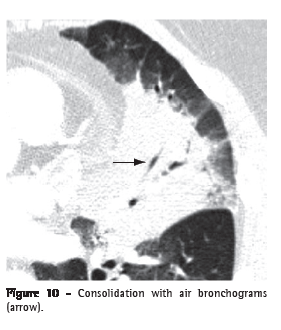

Air bronchogram (broncograma aéreo)

An air bronchogram is the radiological translation of air-filled bronchi, surrounded by sick lung parenchyma, in which the air of the airways has been substituted by any pathological material, radiologically denser than air (e.g., transudate, exudate, blood, accumulation product or neoplastic cells). In general, this is the expression used when a lucent (gas-filled) tubular region is seen within an area of opacified lung (Figures 3 and 10). This tubular image should be of a size and orientation typical of a bronchus or multiple bronchi, presumably representing a segment of the bronchial tree.(22,23)

Consolidation (consolidação)

Consolidation is when the air in the alveolar spaces is supplanted by any type of pathological product, such as inflammatory exudate (pneumonia), transudate (edema), blood (alveolar hemorrhage), lipoprotein (alveolar proteinosis), fat (lipoid pneumonia), cells (bronchioloalveolar carcinoma, lymphoma, organizing pneumonia) or gastric content (aspiration pneumonia).(32) On CT scans, it manifests as increased attenuation of the lung parenchyma, which hinders the visualization of the vessels and outer contours of the bronchial walls. Air bronchograms can be seen (Figures 3 and 10). On CT scans, the attenuation value of the consolidated parenchyma without the use of contrast material is rarely useful for differential diagnosis, with the exception of specific situations (e.g., low attenuation in lipoid pneumonia and high attenuation in amiodarone toxicity).(33,34)